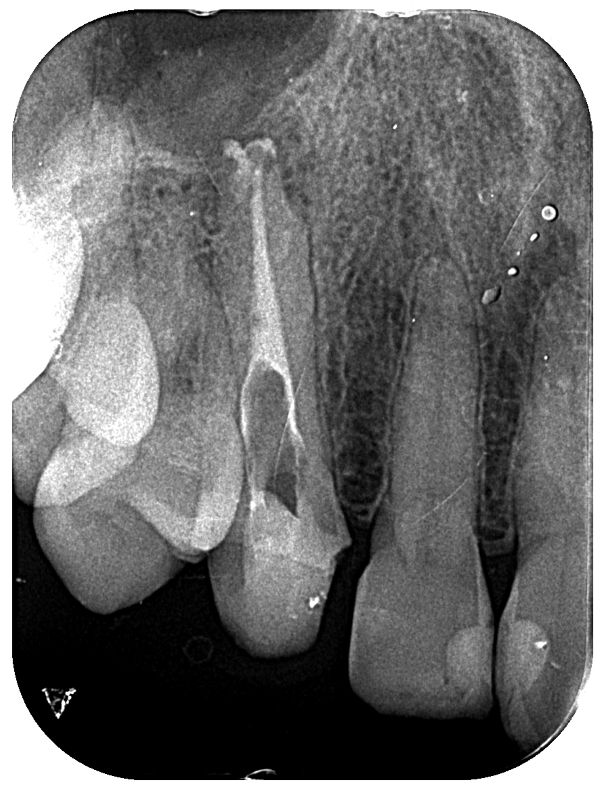

根の中の汚染物質と虫歯菌によって感染してしまった歯質を、徹底的にマイクロスコープ(歯科用顕微鏡)を用いて除去した後、洗浄・消毒を行い、きれいな状態になった事を確認します。(マイクロスコープ下での治療です)

これは歯の根の中の様子です。

通常の根管は白色ですが、真っ黒に変色しております。

上の写真は封鎖材料のガッタパーチャポイントという材料ですが、通常はピンク色です。

取り出した物は茶色く変色していました。

下の写真が汚染物質を取り除いた後の状態です。

ここまで綺麗になってはじめて封鎖します。